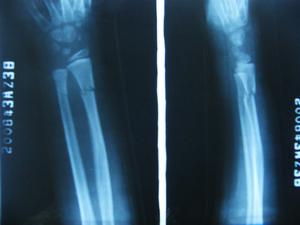

本病根據其外傷病史及臨床表現,可以初步確診但還應使用一些輔助檢查的方法,幫助進一步診斷X線片可明確骨折類型,及移位情況照片,應包括肘腕關節以了解有無鏇轉移位,及上下尺橈關節脫位。

2橈骨骨折;一般使用X線檢查可做出鑑別診斷。